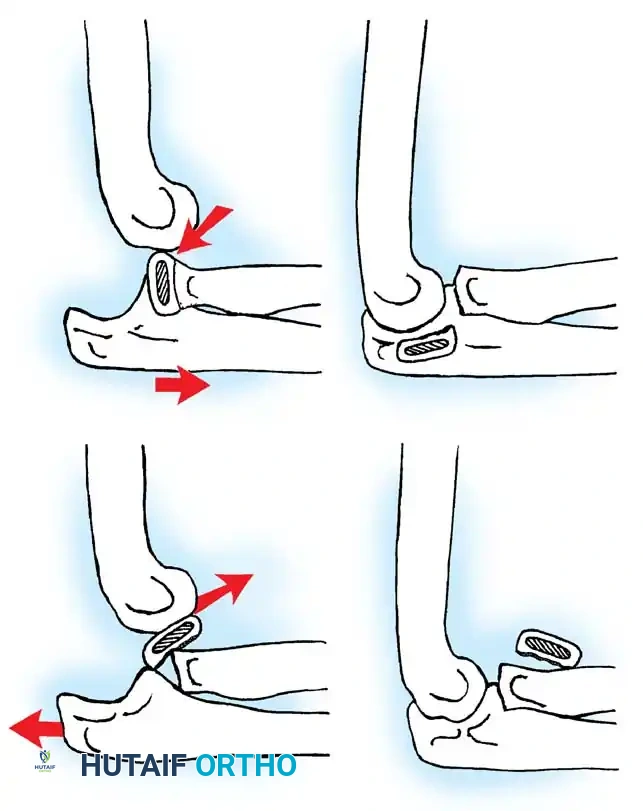

The Metaizeau Technique (Elastic Stable Intramedullary Nailing)

Gonzalez-Herranz et al. and Metaizeau revolutionized the treatment of displaced radial neck fractures (O’Brien types II and III) using retrograde intramedullary pinning. This technique boasts excellent results in over 94% of cases.

- Entry Point: A small incision is made over the distal lateral radial metaphysis, taking care to protect the superficial radial nerve.

- Pin Preparation: A steel Kirschner wire or titanium elastic nail (TEN) is sharply bent at the distal 1.5 cm.

- Insertion: The wire is advanced retrograde through the medullary canal until the bent tip engages the displaced proximal epiphysis.

- Reduction: The pin is rotated 180 degrees around its long axis. The bent tip acts as a cam, elevating the radial head and shifting it medially into anatomical position beneath the lateral condyle.

Fig. 33-44 A-D, Reduction of radial head by leverage method and retrograde intramedullary pinning with Kirschner wire.